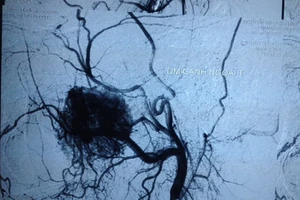

Khối u mũi cực hiếm chỉ gặp ở nam giới tuổi dậy thì